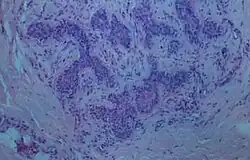

Die Möglichkeit einer Fehlinterpretation des Organs in der Biopsie als karzinomatöse Struktur hat sich bereits ereignet und hatte eine eingreifende Operation zur Folge. In Bezug auf Differentialdiagnosen sind Pathologen und Kieferchirurgen mit der Tatsache konfrontiert, dass in der unmittelbaren Umgebung des juxtaoralen Organs weitere epitheliale Strukturen zu liegen kommen, wie Speicheldrüsen der Backen und epitheliale Nester, die sich aus epithelialen Überbleibseln der Embryonalentwicklung formiert haben.